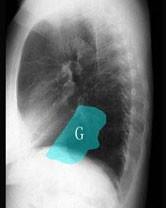

问题 在图所示正常胸部X线影像图像上,该英文字母所代表的肺段为 ( )

选项 A、后基底段 B、背段 C、前基底段 D、外基底段 E、内基底段

答案 C